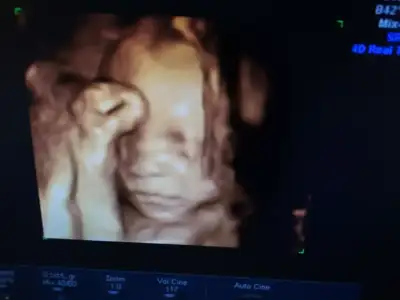

bugün yine hadi bakalım doktorun işi çıktı tüh demezlerse 16:00 detaylı randevum var yine, inşallah bu kez girip güzel haberler ile çıkıp bu konuyu kapatmak nasip olur dua edin